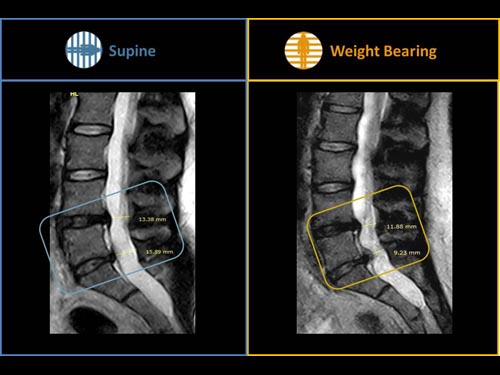

Nová končetinová magnetická rezonance G-scan Brio od společnosti Esaote je tomografický systém MRI, který umožňuje studium všech kloubů i páteře, ať už v klinostatické (vleže) nebo ortostatické (vážící) poloze, protože magnet i pacient se mohou otáčet od 0 do 90 stupňů. Díky inovativnímu designu G-scan mohou být pacienti Brio skenováni v poloze nesoucí váhu, aby se usnadnila diagnostika MSK u těch patologií, které se mohou měnit v důsledku držení těla a polohy, jako jsou bolesti dolní části zad.

• Váhové ložisko: poloha pacienta se stává nedílnou součástí výsledku vyšetření

• Další diagnostické schopnosti: jelikož gravitační síla generuje bio-mechanické změny v anatomii, MR zobrazení v přirozené poloze ve stoje vám umožňuje dosáhnout důležitých dalších informací ve srovnání s tradičními MRI